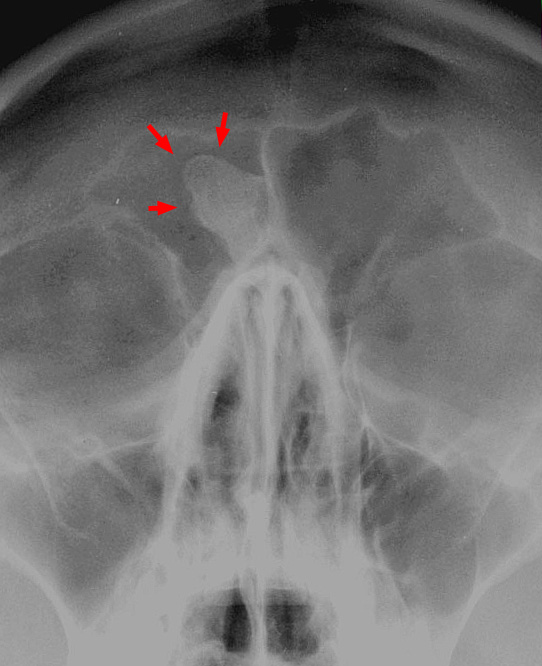

Osteoma is a benign tumor of the bone.

Osteoma most commonly arises on the surface of facial bones.

Osteomas are associated with Gardner syndrome.